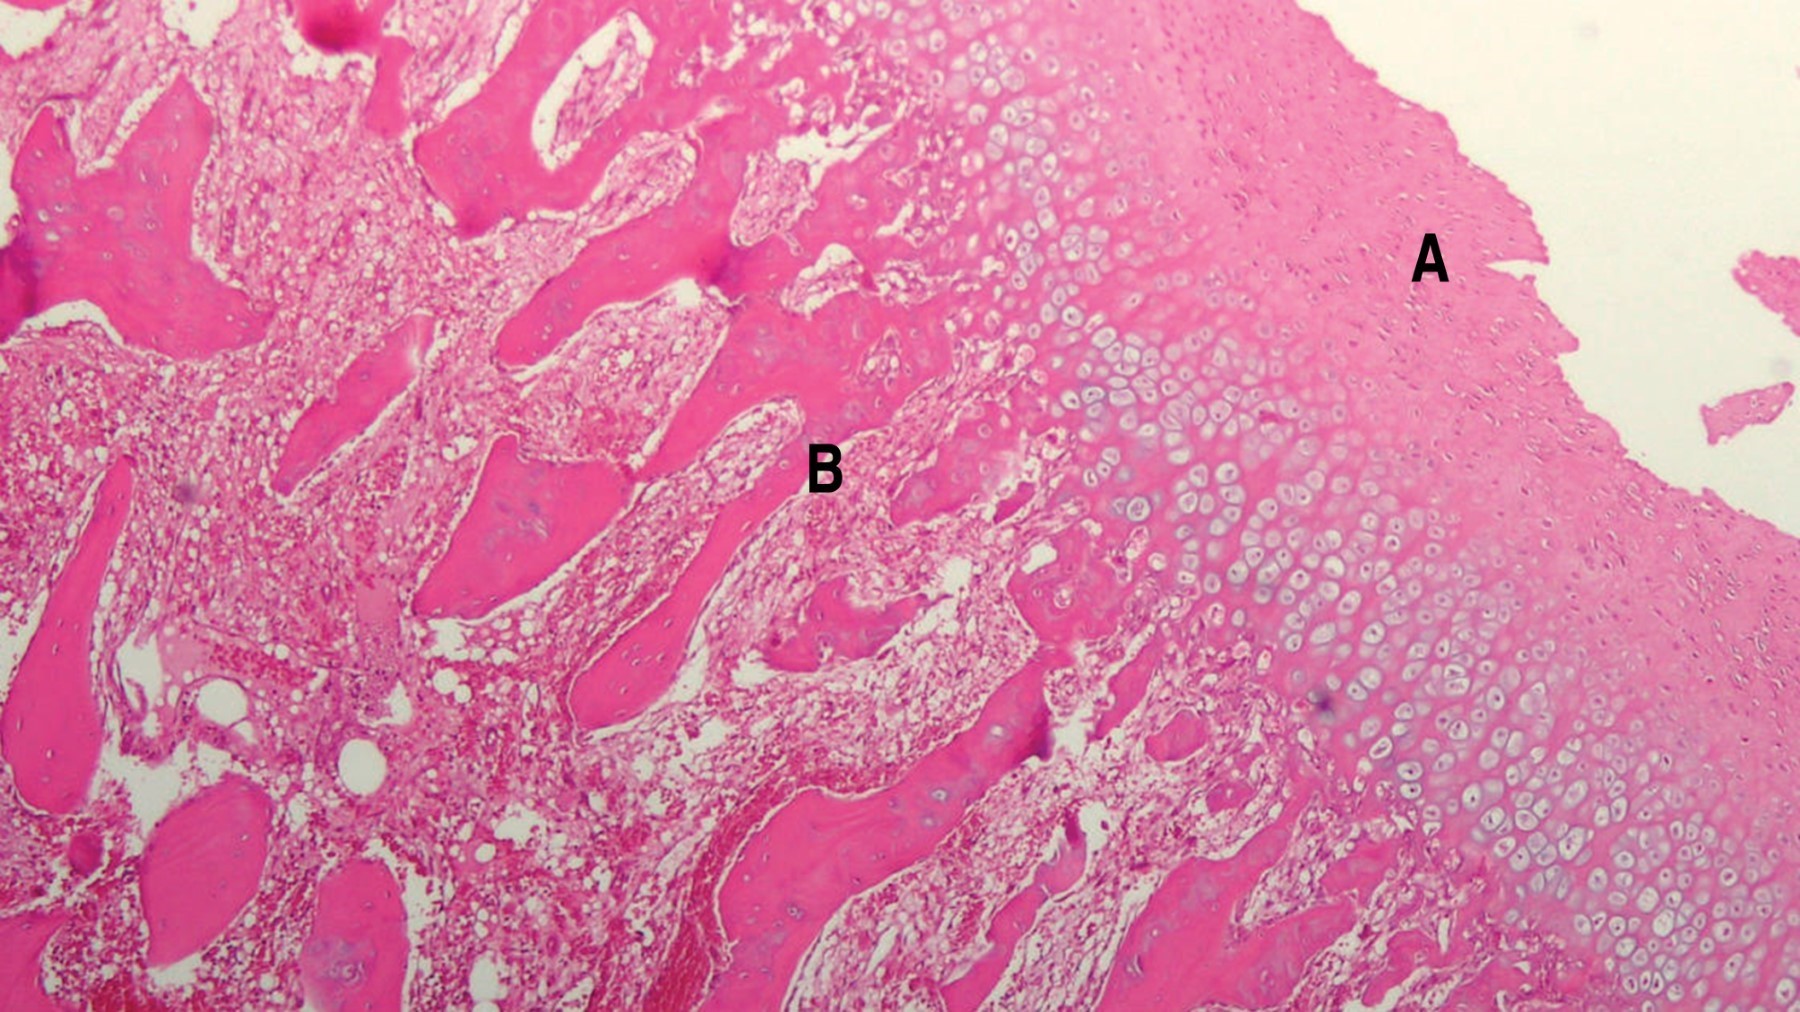

El estudio histopatológico informó un fragmento óseo de 2.5 × 5.5 cm que presenta una formación exofítica grisácea firme con superficie externa irregular. Los cortes histológicos muestran tejido cartilaginoso típico superficial con formación ósea trabecular subyacente típica con escasos focos cartilaginosos intratrabeculares. Diagnóstico osteocondroma (Figura 10).

La histología muestra presencia de trabeculado óseo recubierto por una capa de tejido cartilaginoso y fibroso.4,12